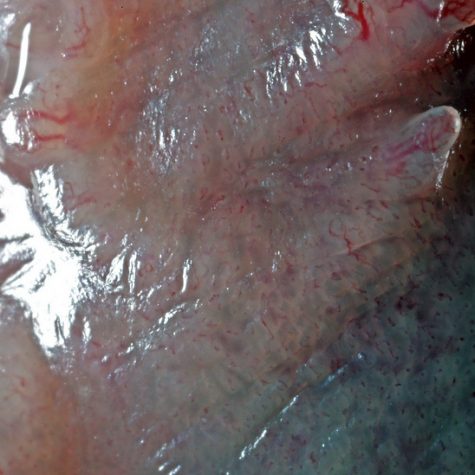

The tongue is a muscular organ in the mouth of most vertebrates that manipulates food for mastication, and is used in the act of swallowing. It is of importance in the digestive system and is the primary organ of taste in the gustatory system. The tongue’s upper surface (dorsum) is covered by taste buds housed in numerous lingual papillae. It is sensitive and kept moist by saliva, and is richly supplied with nerves and blood vessels. The tongue also serves as a natural means of cleaning the teeth.[2] A major function of the tongue is the enabling of speech in humans and vocalization in other animals.

The tongue is a muscular organ in the mouth of most vertebrates that manipulates food for mastication, and is used in the act of swallowing. It is of importance in the digestive system and is the primary organ of taste in the gustatory system. The tongue’s upper surface (dorsum) is covered by taste buds housed in numerous lingual papillae. It is sensitive and kept moist by saliva, and is richly supplied with nerves and blood vessels. The tongue also serves as a natural means of cleaning the teeth.[2] A major function of the tongue is the enabling of speech in humans and vocalization in other animals.

The tongue is a muscular organ in the mouth of most vertebrates that manipulates food for mastication, and is used in the act of swallowing. It is of importance in the digestive system and is the primary organ of taste in the gustatory system. The tongue’s upper surface (dorsum) is covered by taste buds housed in numerous lingual papillae. It is sensitive and kept moist by saliva, and is richly supplied with nerves and blood vessels. The tongue also serves as a natural means of cleaning the teeth.[2] A major function of the tongue is the enabling of speech in humans and vocalization in other animals.

The tongue is a muscular organ in the mouth of most vertebrates that manipulates food for mastication, and is used in the act of swallowing. It is of importance in the digestive system and is the primary organ of taste in the gustatory system. The tongue’s upper surface (dorsum) is covered by taste buds housed in numerous lingual papillae. It is sensitive and kept moist by saliva, and is richly supplied with nerves and blood vessels. The tongue also serves as a natural means of cleaning the teeth.[2] A major function of the tongue is the enabling of speech in humans and vocalization in other animals.

The tongue is a muscular organ in the mouth of most vertebrates that manipulates food for mastication, and is used in the act of swallowing. It is of importance in the digestive system and is the primary organ of taste in the gustatory system. The tongue’s upper surface (dorsum) is covered by taste buds housed in numerous lingual papillae. It is sensitive and kept moist by saliva, and is richly supplied with nerves and blood vessels. The tongue also serves as a natural means of cleaning the teeth.[2] A major function of the tongue is the enabling of speech in humans and vocalization in other animals.

The tongue is a muscular organ in the mouth of most vertebrates that manipulates food for mastication, and is used in the act of swallowing. It is of importance in the digestive system and is the primary organ of taste in the gustatory system. The tongue’s upper surface (dorsum) is covered by taste buds housed in numerous lingual papillae. It is sensitive and kept moist by saliva, and is richly supplied with nerves and blood vessels. The tongue also serves as a natural means of cleaning the teeth.[2] A major function of the tongue is the enabling of speech in humans and vocalization in other animals.

The tongue is a muscular organ in the mouth of most vertebrates that manipulates food for mastication, and is used in the act of swallowing. It is of importance in the digestive system and is the primary organ of taste in the gustatory system. The tongue’s upper surface (dorsum) is covered by taste buds housed in numerous lingual papillae. It is sensitive and kept moist by saliva, and is richly supplied with nerves and blood vessels. The tongue also serves as a natural means of cleaning the teeth.[2] A major function of the tongue is the enabling of speech in humans and vocalization in other animals.